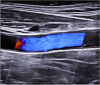

Methods: We included 44 patients with LV-GCA and 42 with high-risk atherosclerosis. US examinations of the axillary, subclavian, and common carotid arteries (CCA) were systematically performed using a MylabX8 system (Genoa, Italy) with a 4-15-MHz probe. IMT ≥ 1 mm was accepted as pathological.

Results: The LV-GCA cohort included 24 females and 20 males with a mean age of 72.8 ± 7.6 years. The atherosclerosis group included 25 males and 17 females with a mean age of 70.8 ± 6.5 years. The mean IMT values of all arteries included were significantly higher in LV-GCA than in atherosclerosis. Among LV-GCA patients, IMT ≥ 1 mm was seen in 31 axillary, 30 subclavian, and 28 CCA. In the atherosclerotic cohort, 17 (38.6%) had IMT ≥ 1 mm with axillary involvement in 2 patients, subclavian in 3 patients, carotid distal in 14 patients (5 bilateral), and isolated carotid proximal affectation in 1 case. A cutoff point greater than 1 pathological vessel in the summative count of axillary and subclavian arteries or at least 3 vessels in the count of six vessels, including CCA, showed a precision upper 95% for GCA diagnosis.

Conclusion: The IMT is higher in LV-GCA than in atherosclerosis. The proposed US halo count achieves an accuracy of > 95% for the differential diagnosis between LV-GCA and atherosclerosis. The axillary and subclavian arteries have higher discriminatory power, while carotid involvement is less specific in the differential diagnosis.